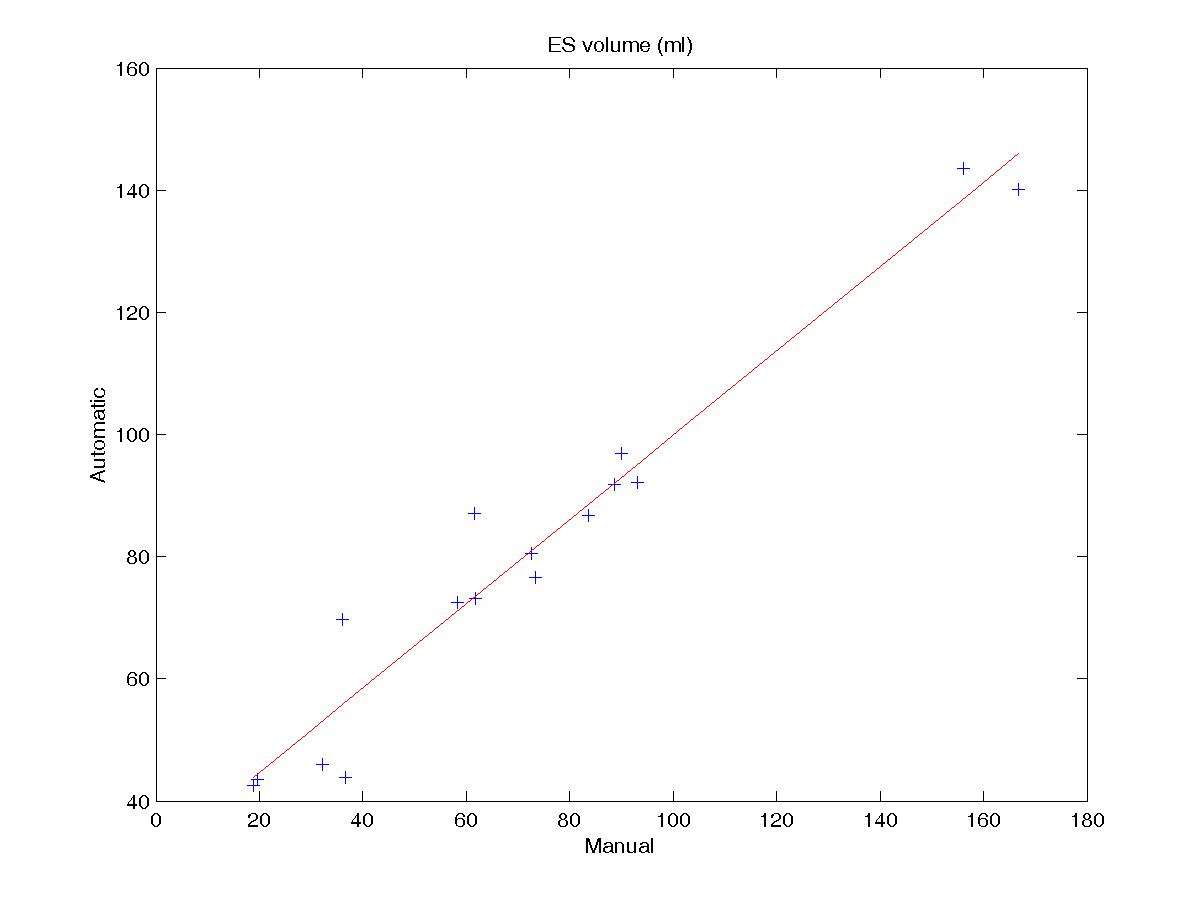

Figure 4 shows the regression plots for the endocardial volume at ED and ES. For both cases, the regression coeffictient is good (0.96 and 0.97 respectively) and the spread of the values is relatively low, demonstrating that the influence of the poor segmentation in the apical slices doesn’t have much influence in the endocardial volume estimation. Errors obtained in the computation of the ejection fraction (EF) and ventricular mass (VM), which are based on volume estimations, are reported in table 3.